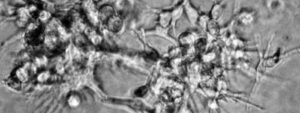

Escac i mat a les metàstasi en el cervell

Les metàstasis al cervell tenen un origen i perfil genètic diferent al dels tumors primaris. [...]